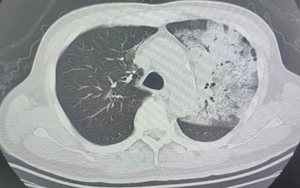

Người đàn ông sốt 40 độ C, phổi gần như 'trắng xóa", chỉ vài ngày đã suy đa tạng: Thủ phạm liên quan đến thói quen nhiều gia đình vẫn mắc

Sống khỏe 2026-03-10T07:00:00Một chiếc điều hòa lâu ngày không được vệ sinh có thể tiềm ẩn rủi ro sức khỏe nghiêm trọng mà nhiều người không ngờ tới.